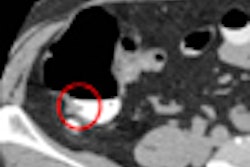

In other VC news, investigators from Korea report that thinner CT slices are far more important for lesion detection than low noise, which had very little effect on sensitivity. Click here to read the article, or visit our Virtual Colonoscopy Digital Community at vc.auntminnie.com.